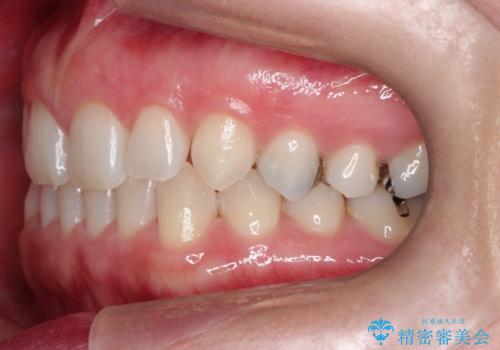

- 前歯の正中離開(すきっ歯)の改善を希望され来院された患者様です。

初診時の歯並びの状態としては、上顎中切歯間に1mm程の隙間があり、その他に見た目に関して気になるような問題点はない状態でした。

インビザライン(マウスピース)にて上顎のみの矯正治療を行いました。